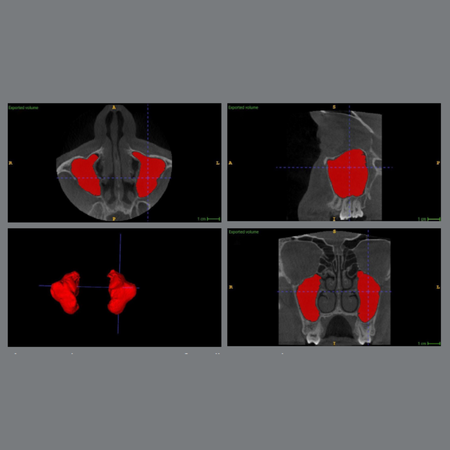

Alterações volumétricas no seio maxilar após desimpacção ortodôntica de caninos superiores impactados unilateralmente: um estudo prospectivo de boca dividida baseado em tomografia computadorizada de feixe cônico

Introdução: A relação entre a desimpacção ortodôntica de caninos superiores (CSs) impactados unilateralmente e as alterações volumétricas no seio maxilar (SM) permanece pouco explorada. Objetivo: Este estudo teve como objetivo avaliar as alterações volumétricas do SM após a tração ortodôntica de CSs impactados, utilizando tomografia computadorizada de feixe cônico (TCFC). Adicionalmente, examinou as diferenças com base no local da impacção (vestibular vs. palatina) e no...